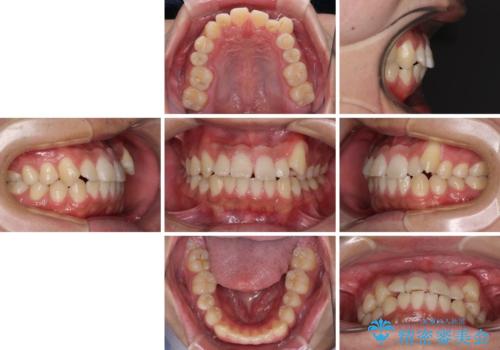

目立つ八重歯を非抜歯矯正で整える 目立たないワイヤー矯正

- 八重歯と前歯の隙間を気にして来院された患者様です。

八重歯の改善のため、奥歯を後方に移動させていくこととし、患者様と相談の上、ワイヤー装置にて矯正治療を行うこととしました。

治療装置については、自己管理が煩わしいとのことで、マウスピースではなく目立ちにくいワイヤー装置を選択されました。

上顎前歯正中の隙間は、舌突出癖によるものと考えられ、舌のトレーニングによる悪習癖改善が必須であるため、徹底するよう指導してから治療を開始することとしました。